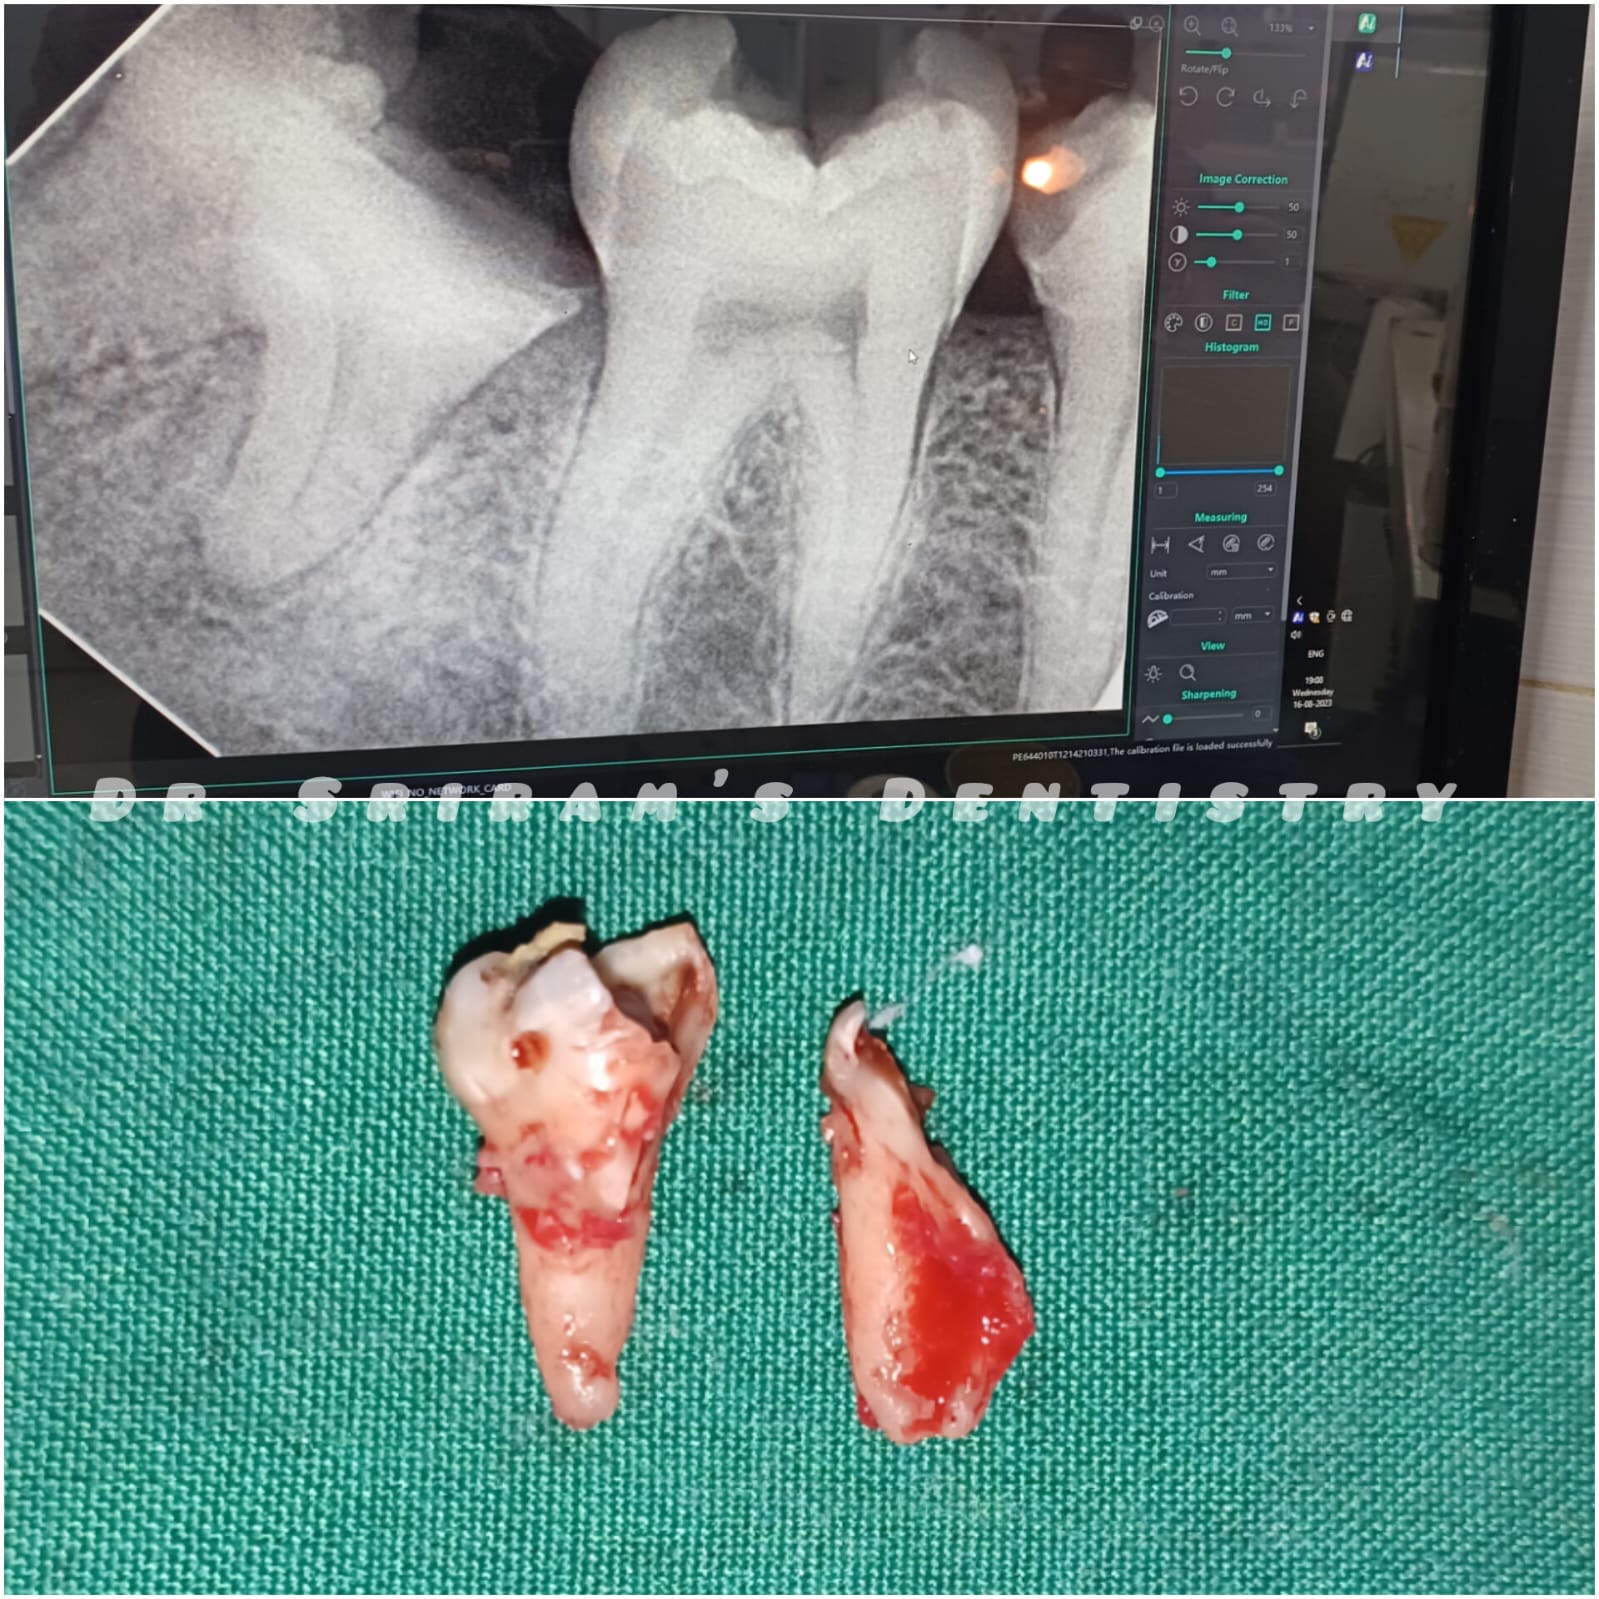

Gallery Home Gallery Pulpectomy Broken File Retrieval Root Canal Treatments Orthodontic Treatments Wisdom Teeeth Removal